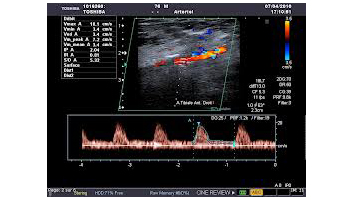

- Echodoppler des artères rénales

- Doppler artériel ou veineux des membres inférieurs

- Doppler artériel ou veineux des membres supérieurs

- Doppler des troncs supra aortiques